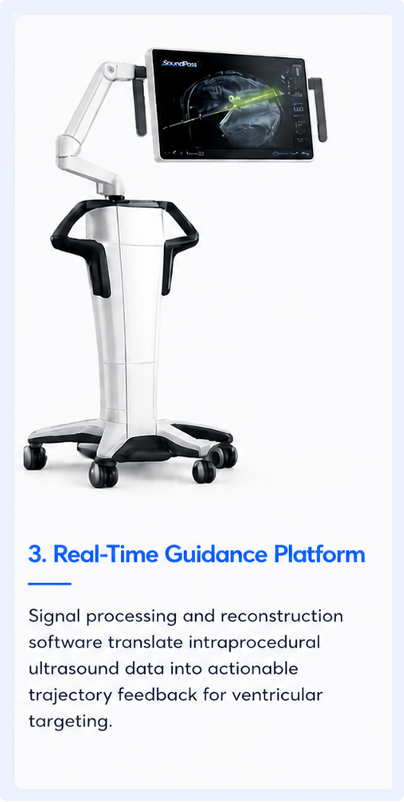

Our team is building the world’s first ultrasound and reconstruction algorithm capable of 3D imaging from an astounding 1.65mm diameter transducer. This provides neurosurgeons the tools they need for successful EVD placement in even the most challenging situations.

Three integrated technologies designed to make ventricular access visible in real time